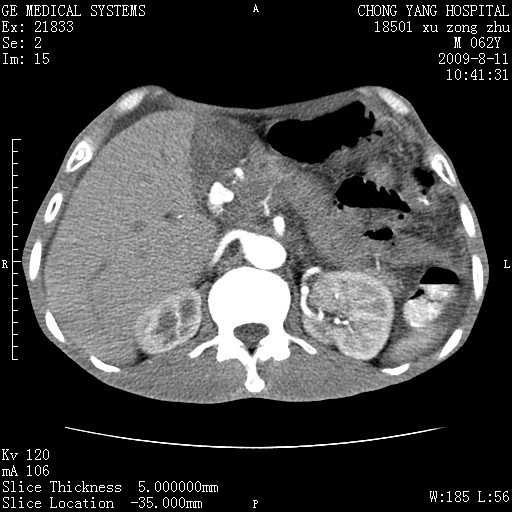

以下是引用杀毒软件在2009-8-11 16:35:00的发言:[br]肝内胆管扩张局限于左叶,胆管内有结石伴肝外胆管结石,胆管壁增厚呈弥漫性并发腹腔积液,胰腺边界模糊。[br][br]考虑---胆总管及肝内胆管结石继发胆管炎及胰腺炎,左肾下极囊肿,腹水。

以下是引用zjzjr在2009-8-11 17:35:00的发言:[br]肝内胆管扩张局限于左叶,胆管内有结石伴肝外胆管结石,胆管壁增厚呈弥漫性并发腹腔积液。[br][br]考虑---胆总管及肝内胆管结石继发胆管炎,左肾下极囊肿,腹水。